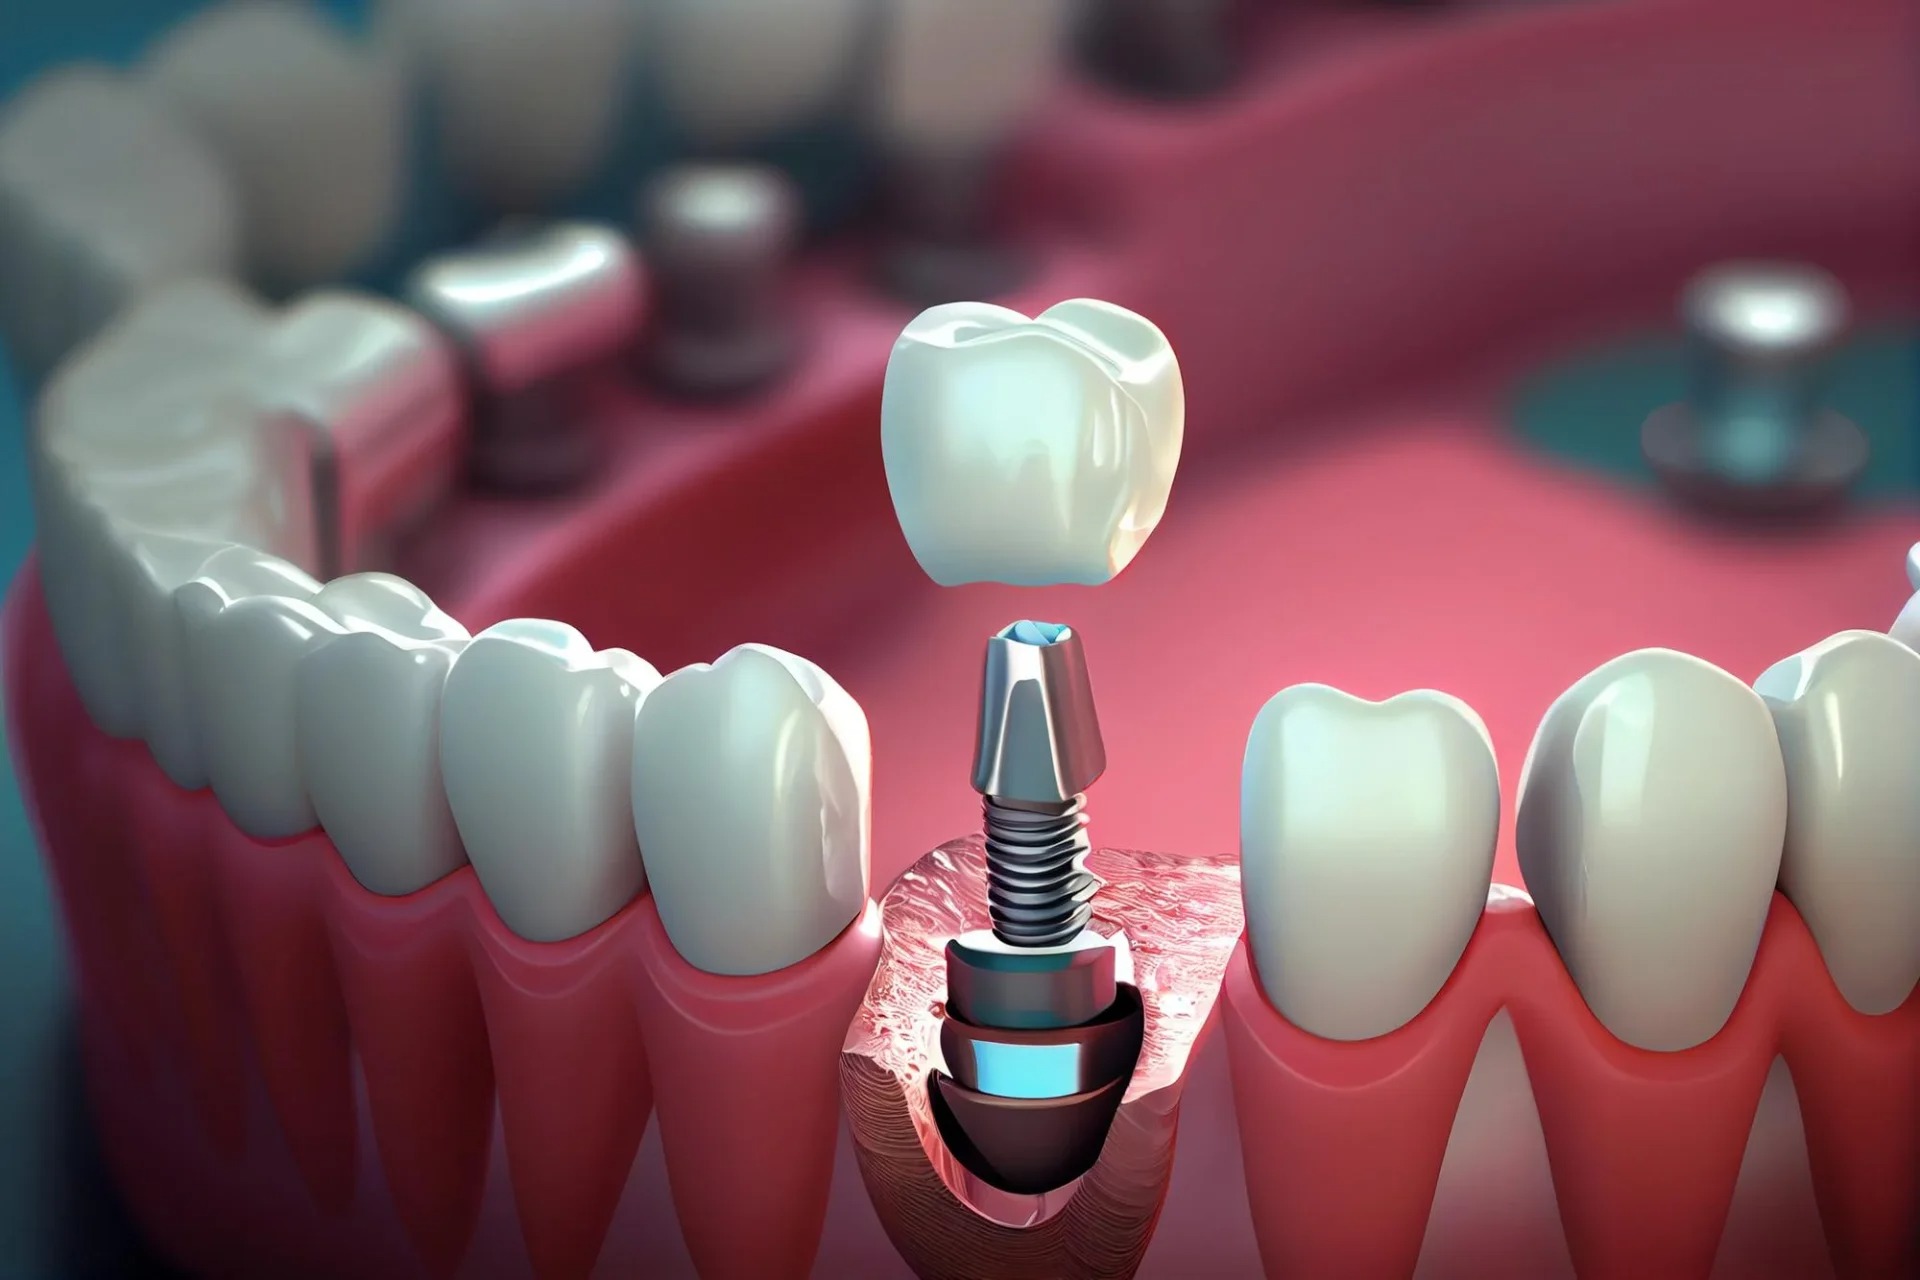

Titanyum materyalden üretilen ve vida benzeri olan malzeme çene kemiğine yerleştiriliyor ve sonrasında üzerine protez diş yerleştiriliyor. Eksik diş sorununa mükemmel bir çözüm sunan implantın gerçek bir diş gibi kullanılabiliyor olması, estetik açıdan gayet başarılı olması da önem taşıyor.

Dental implant, eksik dişlerin yerine estetik ve fonksiyonel olarak en yakın çözümü sunan, titanyumdan üretilmiş yapay diş köküdür. Çene kemiğine yerleştirilerek üzerine protez diş yapılır. Hem çiğneme fonksiyonunu geri kazandırır hem de doğal diş görünümü sağlar.

İmplant yerleştirme işlemi lokal anestezi ile yapılır, bu nedenle hasta işlem sırasında ağrı hissetmez. Cerrahi sonrası hafif ağrı ve şişlik görülebilir, ancak bunlar reçete edilen ilaçlarla kontrol altına alınabilir. Tedavi süresi genellikle 2-4 ay arasında tamamlanır; bu süre, kemiğin implanta kaynaşması (osteointegrasyon) sürecine bağlıdır.